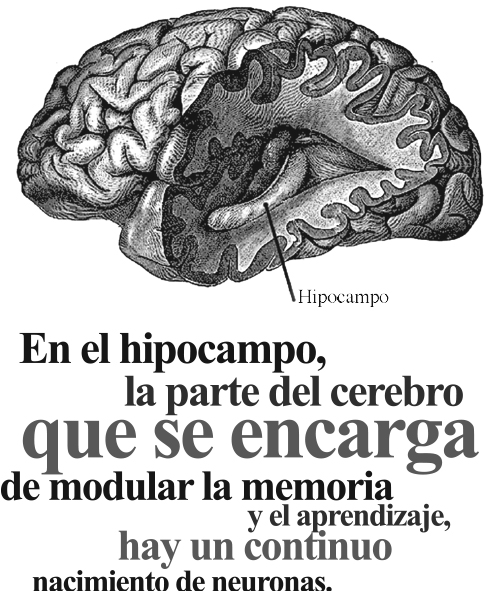

Hasta hace menos de tres décadas la ciencia no aceptaba el hecho de que la producción de neuronas (neurogénesis) en la edad adulta es posible. Hoy se sabe que el cerebro está en continua evolución a lo largo de toda la vida de un individuo y que la generación de nuevas neuronas está íntimamente relacionada no sólo con los genes sino también con el entorno.

“Pero cuando se genera desordenadamente a causa de un estrés crónico, provoca la disminución en el número de neuronas, particularmente en el hipocampo, un fenómeno que se ha relacionado con la depresión, alteraciones del sueño y aumento de peso entre otros efectos”.

A la fecha no se ha logrado observar neurogénesis en todas las regiones del cerebro. La literatura científica registra dos zonas en particular: el bulbo olfatorio y el hipocampo; sin embargo, hay trabajos que hablan de proliferación de neuronas en otras regiones del sistema nervioso, tales como el tallo cerebral, la sustancia negra y la médula espinal.